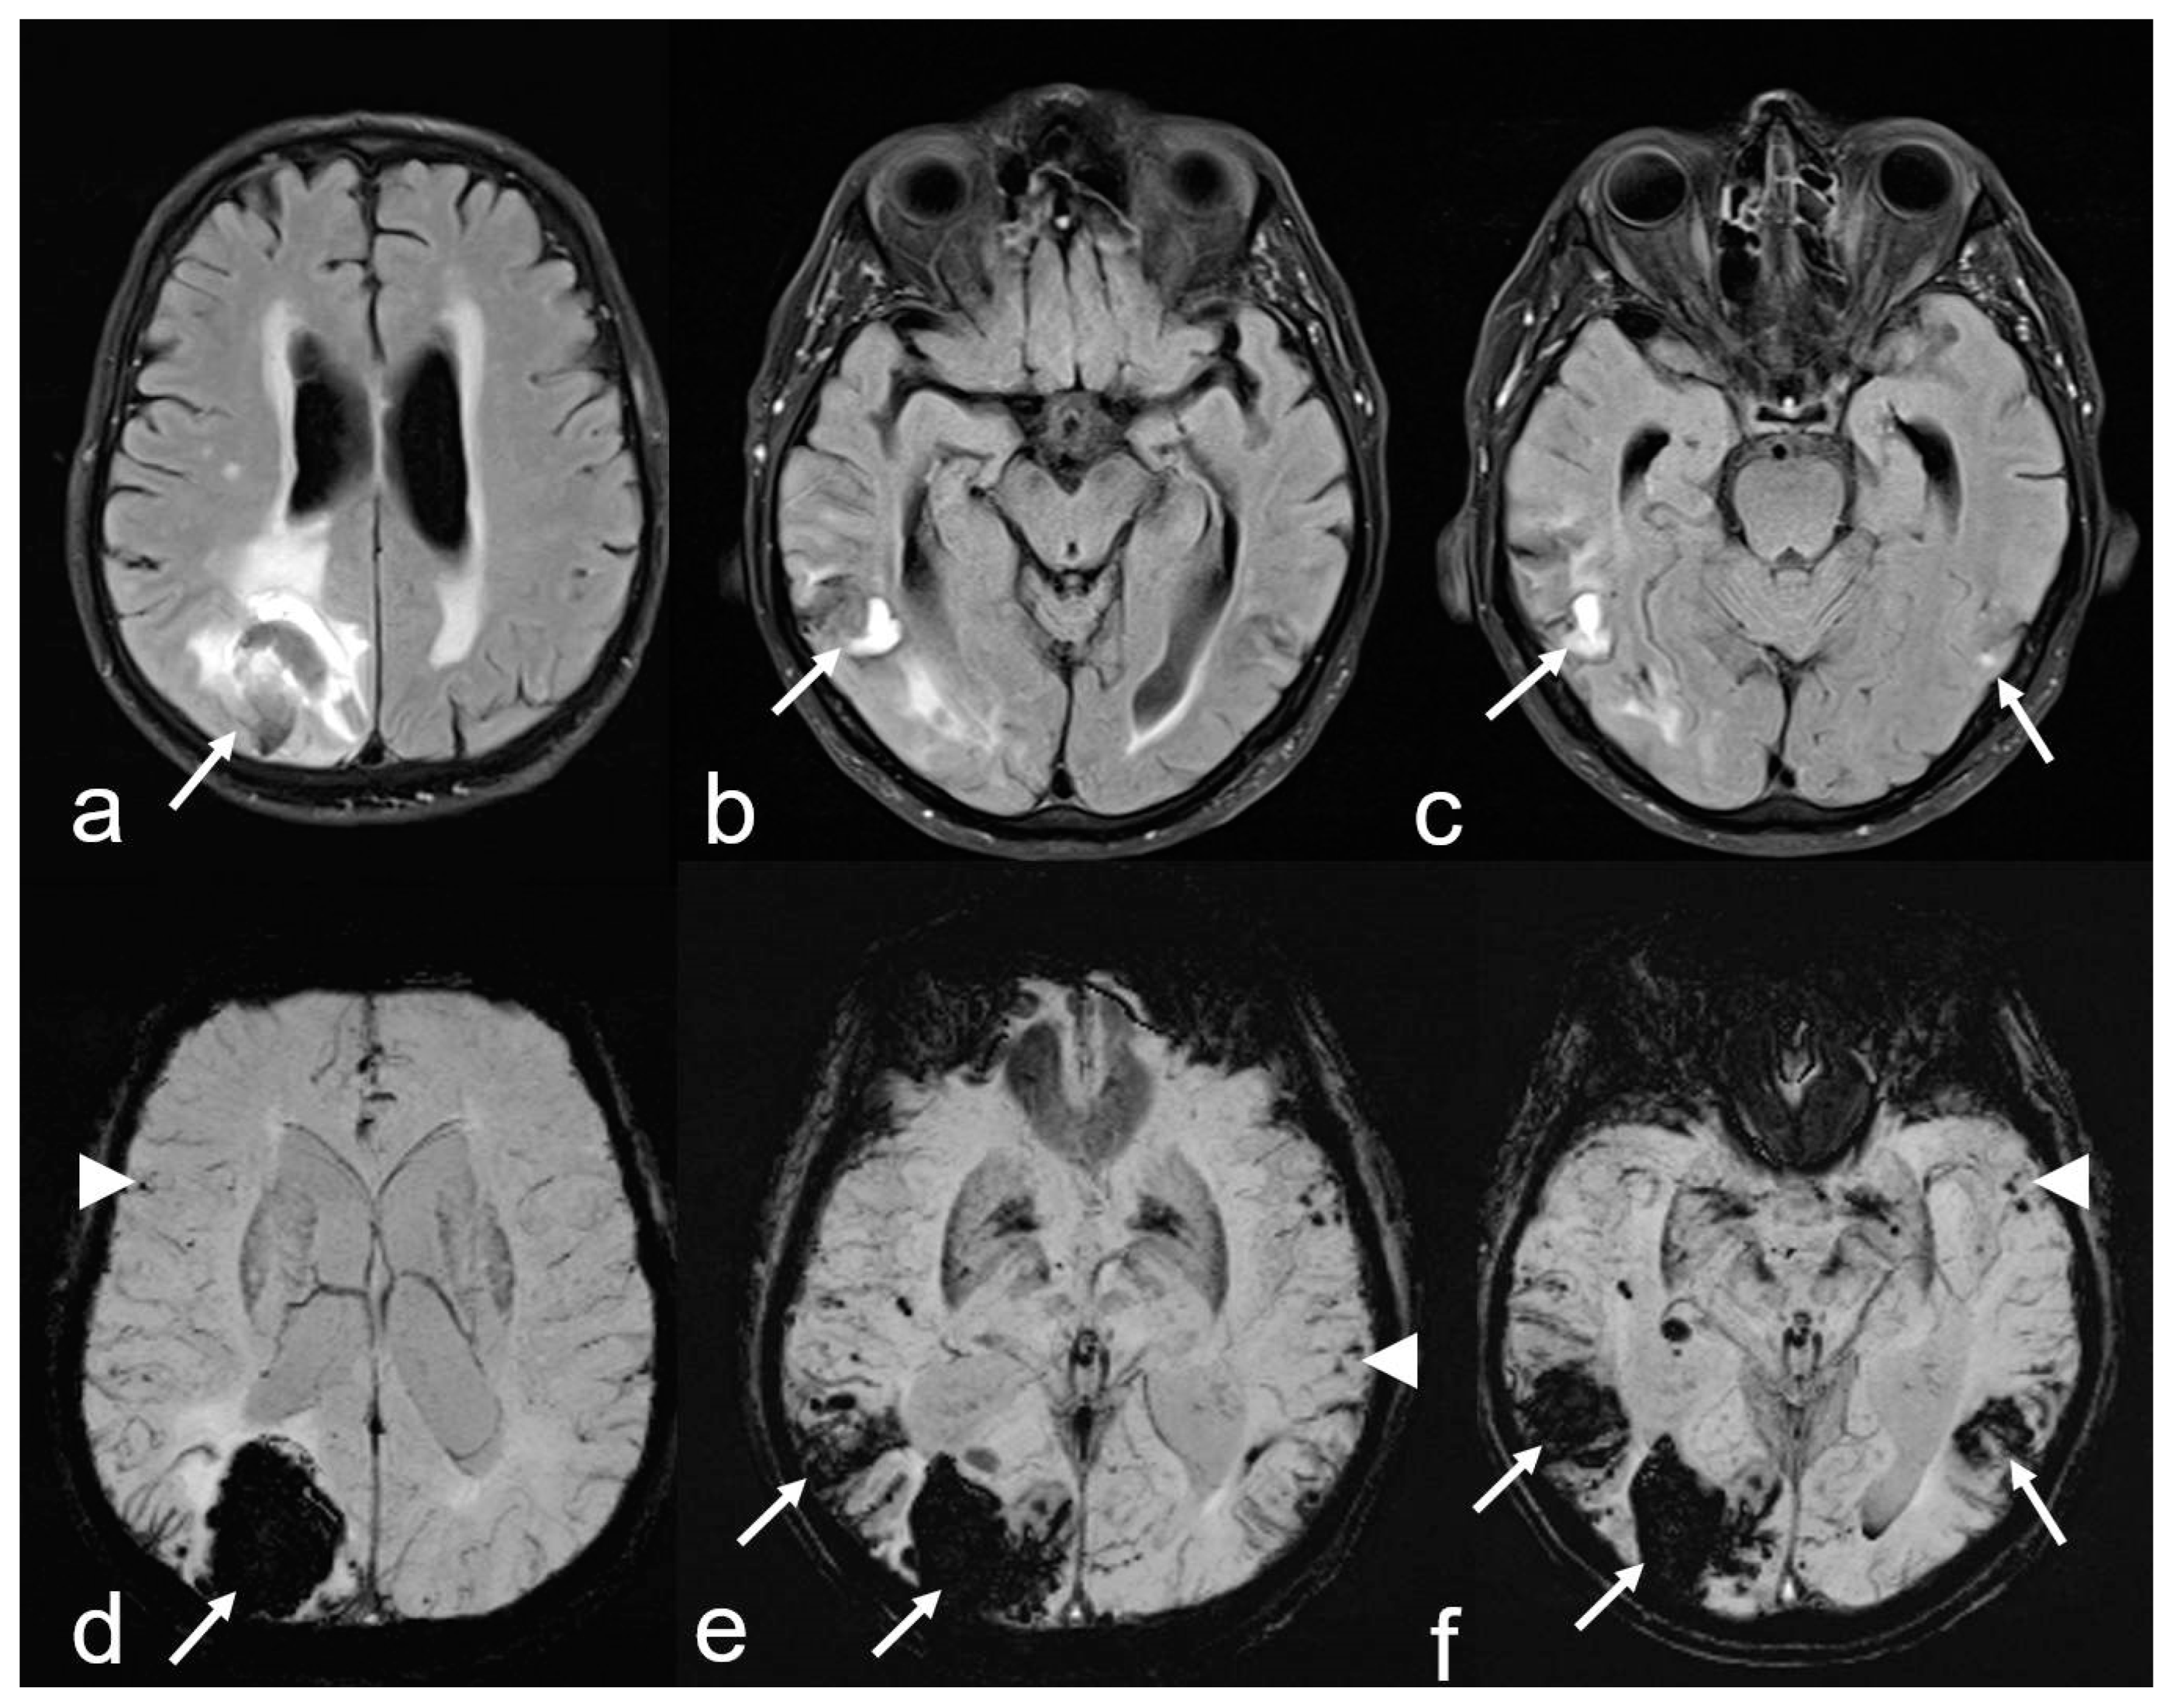

Figure 3.

Cerebral amyloid angiopathy (CAA) and Alzheimer’s disease (AD) in an 82-year-old woman with progressive cognitive decline and short-term memory disturbance. Axial T2-weighted images (WI) (a,b) showing distinct temporal mesial atrophy ((a), arrowhead), enlarged temporal horns ((a), arrow), vascular leukoencephalopathy ((b), arrowhead) and enlarged perivascular spaces (PVS; (b), arrow). Susceptibility-weighted imaging (SWI) ax. (c,d) disclosing multiple cortical and subcortical microbleeds (MB) (arrow), especially temporal and parietal; MRI 1.5 T Siemens AREA.

2. Cortical and subcortical microbleeds (MB), which have been identified as a risk factor for lobar ICH and ischemia, have also been associated with cognitive impairment [38,53,54,55]. In contrast to hypertensive microangiopathy caused by lipohyalinosis, which typically affects the basal ganglia, thalamus, pons and cerebellum [55,56,57,58,59,60], MB are generally absent in these regions in CAA [38,54,61]. Due to the neurodegenerative and cerebrovascular processes associated with Aß deposits, MBs are preferentially localized in the parieto-occipital regions in both CAA and AD (Figure 1, Figure 2 and Figure 3) [3,19,53,54,61].